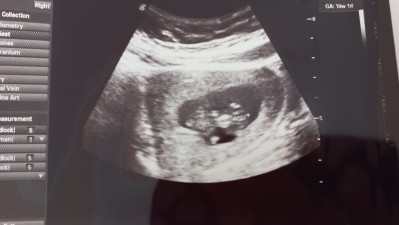

Arkadaşlar 1 dk bile bakmadı sağ olsunlar sak sak çekti verdi bunun neresi kafa neresi ayak hiç ilgilenen adam akıllı doktor yok az iyi olanlar da muanesi 300 lira ultroson fotoğrafı bakabilir misiniz neresi kafa

Gebelik haftası 10+3

Henüz belirgin olması için haftanız çok erken daha. Ama muhtemelen sol taraf kafası çünkü daha yuvarlak duruyor. Bide devlet hastanesinin çektiği ultrason görüntüleri zaten bebek seklinde pek çıkmıyor bu neresi diye kağıda bakıp duruyorsun

Canım keşke devlet olsa özeldi ama devletten beterdi sanırım dediğiniz gibi sol taraf kafası ve fotoğrafta arkası dönük sanırım

Canim bu haftada doktorlar cok bilgi vermez zaten bu haftada ayaklari kollari tam belli olmaz buyuk olan kisim kafadi bu haftalarda kafasi bedeninden buyuk olur ben 12 haftada gittim doktor daha gelisimini konusmamiz icin cok erken 1 ay sonra gel herseyi gostericem o zaman net konusicaz dedi kemikleri olusmadigi icin makinelerde zaten tam olcum yapmio yablisliklar olabiliyot bu haftalarda dedi

Canım ultrosona doğru baktığımda kafası ayaklari belliydi hareket ettiriyodu bu ultoroson kağıdında da arkası dönük o yüzden belli değil diye düşünüyorum ama beklemedi hemen çekti bıraktı uzakta bir özel doktora gitmiştim kadın 10 dk ileri geri yaptı aleti önüne dönmesini bekledi net boy ölçümü almak için uzak olmasa oraya devam edicem ama her seferinde gözüm yemiyor yakınlarda iyi bir doktor arastirmam lazım